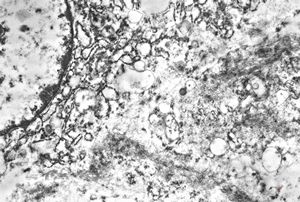

F,25y. | myopathy - atrophic and regenerating muscle cells

M,2y. | myopathy - regenerating muscle cell